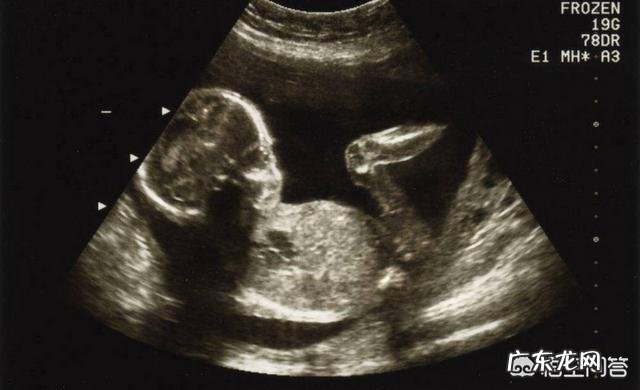

你好,我是一名超声科医生,很高兴回答你的问题 。其实B超对于胎儿并没有什么危害 。因为B超是一种波,而且医用超声波是低强度的,一般只要不长时间,反反复复的接触,问题是不大的 。但是为了安全起见,一般妊娠三个月之内,没有特殊需要,最好不要反复做超声检查,因为前三个月是胎儿发育最关键的时期,这段时间的胎儿比较“娇嫩”,在其发育阶段,最好不要给予太多干扰 。

目前B超检查是很规范的,有很合理的时间安排,一般正规的医院都有一系列的流程,只要按照流程走,一般就是比较全面的产检了,出现畸形的可能就会降低很多 。

主要分为早孕(10~14周,主要是确诊宫内妊娠,单双胎,活胎),中孕(20~26周,是脊柱裂,单腔心等畸形筛查的关键时期),晚孕(32~36周,主要是为了检测胎儿的生长发育情况,胎盘的成熟度等等) 。

孕期B超检查对胎儿的影响应该不大的 。有些检查是十分必要的,孕期B超是对自己和宝宝负责任的做法 。不用过于担心 。